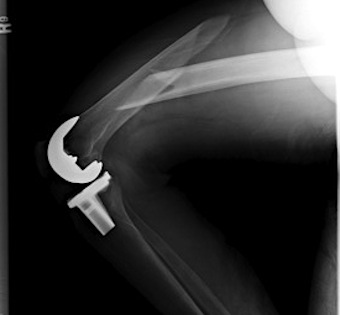

3.  Anterograde nail

Indications

- sufficient bone above implant for distal locking

Issues

- stress riser between femoral implant and nail

- must ensure correct alignment

TKR Femoral FractureTKR Femoral Nail APTKR Femoral Nail Lateral